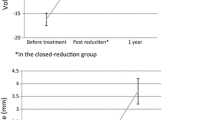

Dorsal angulation, radial inclination and ulnar variance were assessed on conventional radiographs of a cohort of 251 patients, 38 men and 213 women, to determine the anatomic position of the DRF at presentation (primary position) and during follow-up.

Secondary fracture displacement was assessed in the non-operatively treated patients (N = 154) with an acceptable position, preceded (N = 97) or not preceded (N = 57) by primary reduction (baseline position). Additionally, bone microarchitecture and calculated bone strength at the contralateral distal radius and tibia were assessed by HR-pQCT in a subset of, respectively, 63 and 71 patients.

Secondary fracture displacement

Reduction was conducted in 120/135 patients with a primary unacceptable position with a success rate of 75%. This resulted in 206 patients with an acceptable baseline position. In 20 patients, surgery was conducted because of comminution of the fracture or patients’ preference. One patient had a fracture with 20 degrees volar angulation and, therefore, underwent surgery. After exclusion of these 21 patients and 31 patients without follow-up, 154 were eligible and assessed for secondary fracture displacement. Median follow-up with radiographs was 35 days (interquartile range 45 days), with numerous follow-up visits in this time range (Fig. 3). Secondary displacement occurred within the first 2 weeks in 39 patients (67%), in the third week in 12 patients (21%) and seven patients (12%) had a DRF displacement after 1 month. When comparing patients with secondary fracture displacement (N = 58) to those without (N = 96), we found no differences for age, gender distribution, BMI, BMD, number and severity of VFs, smoking, alcohol intake, calcium intake and vitamin D levels (Table 1). Primary reduction was significantly associated with secondary DRF displacement [OR 12.53 (95% CI 4.60–34.09), p < 0.001] in 154 patients.

At the distal radius (measured in 30 patients), total [OR 0.27 (95% CI 0.10–0.73), p = 0.010] and cortical [OR 0.31 (95% CI 0.12–0.80), p = 0.016] vBMD and cortical thickness [0.32 (95% CI 0.13–0.80), p = 0.015] were significantly lower in patients with secondary dislocated fractures. There were no differences for trabecular parameters and micro-FEA. The strongest determinant for secondary fracture displacement was primary reduction [OR 22.00 (95% CI 2.27–212.86), p = 0.008]. After adjustment for primary reduction, total [0.16 (95% CI 0.04–0.68), p = 0.013] and cortical [0.19 (95% CI 0.05–0.80), p = 0.024] vBMD and cortical thickness [0.13 (95% CI 0.02–0.74), p = 0.021] were significantly associated with secondary fracture displacement. Adjustment for age did not change the association of HR-pQCT parameters with secondary displacement of a DRF [Table S-2].

At the distal tibia (measured in 36 patients), total vBMD [OR 0.35 (95% CI 0.13–0.92), p = 0.034] and cortical pore diameter [OR 0.37 (95% CI 0.14–0.94), p = 0.036] at the distal tibia were significantly lower in patients with secondary dislocated fractures, while there were no differences for trabecular parameters and micro-FEA. After adjustment for primary reduction, both total vBMD [OR 0.06 (95% CI 0.01–0.64), p = 0.020] and cortical thickness [OR 0.22 (95% CI 0.06–0.84), p = 0.027] were significantly associated with secondary fracture displacement. After adjustment for age, none of the HR-pQCT parameters at the distal tibia was significantly associated with secondary displacement of a DRF [Table S-3].